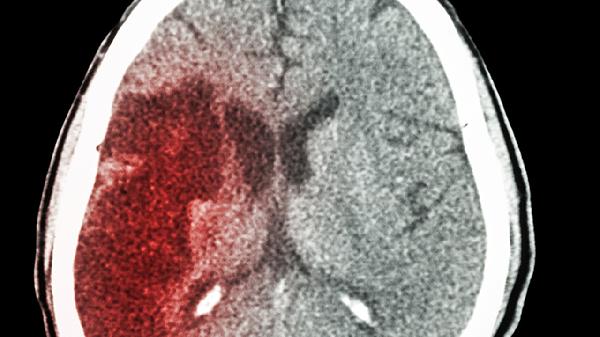

车祸导致脑出血开颅手术后能恢复吗

大多数接受车祸导致脑出血并进行开颅手术的患者,能够实现部分或完全的功能恢复。恢复的程度主要受到出血位置、手术时间、康复治疗、年龄和基础健康状况以及并发症管理等因素的影响。

1、出血部位:

比如基底节区出血可能会留下肢体无力的问题,而脑干出血则可能影响呼吸和血液循环。额叶受损的话,更容易出现认知方面的问题。不同脑区的代偿能力也有所不同,例如非优势半球的语言区域受损后,康复的可能性反而更高。